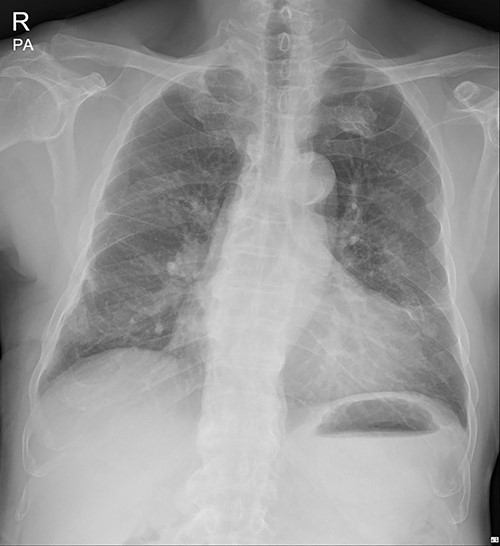

The patient visited the outpatient clinic on 07 March 2022, for stitches removal, complaining of mild discomfort on the operation site (Fig. 3.). Chest X-ray showed a large, localized submuscular emphysema between the rib cage and the SAM. The surgical wound was clear. Stitches were removed as planned, and the patient was asked to revisit the outpatient clinic 3 days later.

Immediate postoperative chest X-ray after plates removal (24 February 2022).